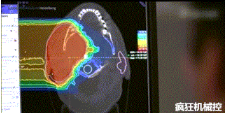

▲360°重離子治療一體機治療腫瘤

360°重離子治療一體可從任何角度用重離子(碳,氦,氧)和質(zhì)子(氫)照射腫瘤。此外,基于機器人的治療臺可以通過六種方式進行調(diào)整。

▲360°重離子治療一體機治療患者

光柵掃描被集成到360°重離子治療一體機中,這種極其精確的照射方法以毫米為單位掃描腫瘤,可以保護健康組織且只治療腫瘤區(qū)域。

特別是腫瘤在高度輻射敏感位置或者諸如視神經(jīng)附近的復(fù)雜位置,可以通過選擇最佳射束入射角來減小這些器官的損傷。